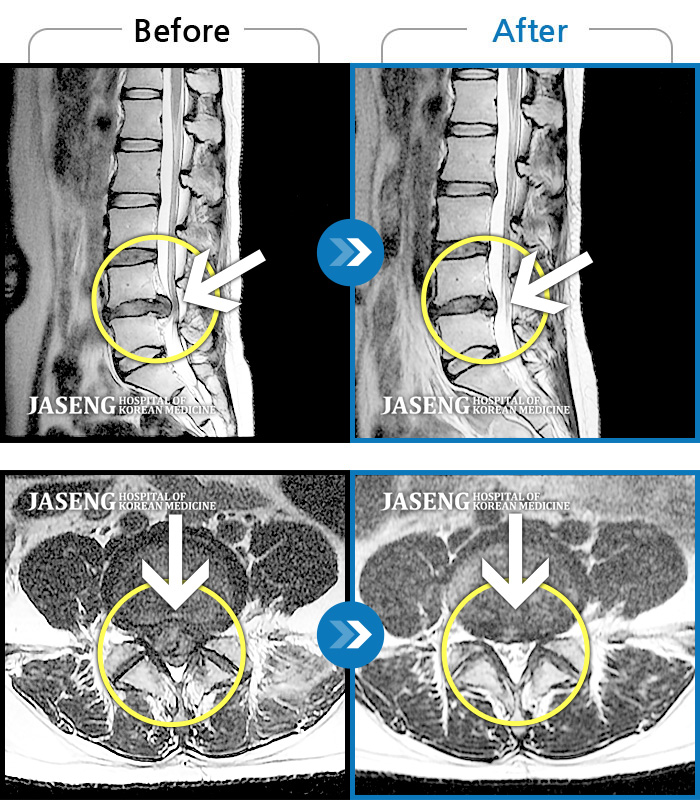

Before

After

환자에게 사전 동의를 받아 동일 조건에서 촬영되었습니다.

개인에 따라 치료 후 부작용이 발생할 수 있으니 의료진과 상담 후 치료를 진행하시기 바랍니다.

허리 우측부터 골반까지 통증, 우측 하지 저림 증상

우측 허리와 골반이 아프고, 우측 하지 후면으로 통증이 있다.